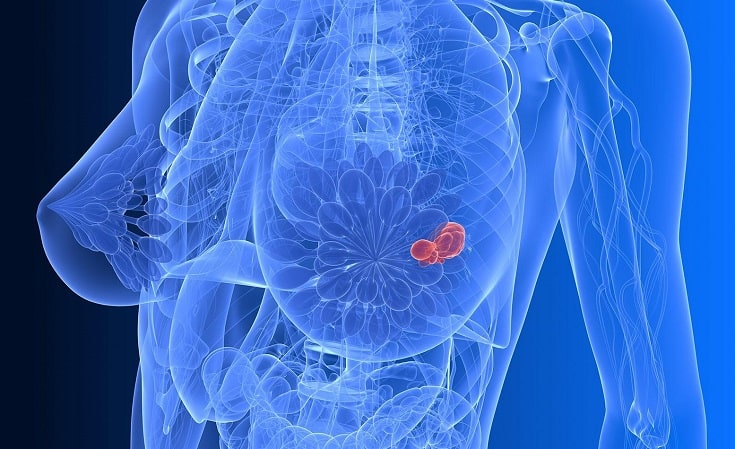

Патологию необходимо дифференцировать от воспалительного процесса. А также отличить доброкачественное от злокачественного образования.

Диагностика образований включает:

- Ультразвуковое исследование протоков железы. Показывает наличие в патологической полости жидкости или ее плотную структуру.

- Маммография на рентгеновском аппарате. Скрининговый метод, используется для женщин от 40 лет.

- Аспирационная биопсия с лабораторным исследованием содержимого. Биоптат забирается тонкой иглой под местной анестезией. Онконастороженность оправдана, т.к. заболевание может стать причиной 3-5% случаев онкологии молочных протоков железы.